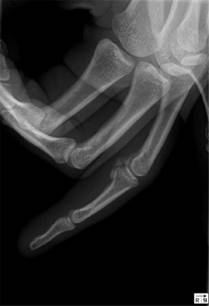

A 25-year-old right-hand dominant black woman, who works as a waitress, was observed in the emergency room (ER) after an acute trauma of the fourth finger of the right hand. The patient reported no relevant medical history. She experienced pain on palpation of the volar aspect of the PIP joint, where a soft tissue mass was present. On the radiograph of the hand, an abnormal lesion compatible with a calcification could be seen on the volar side of the PIP joint of the fourth finger; there was no periosteal reaction, evidence of joint space narrowing or cortical lesion, and the calcification was separated from the bone (Figure 1). The patient was discharged with recommendations for analgesia and syndactyly.

Figure 1:Acute calcific periarthritis in the proximal interphalangeal joint of the fourth finger of the dominant hand of a 25-year-old black female, at the emergency room evaluation (lateral view).

The patient returned to the ER after two days referring worsening of the pain at the PIP joint. This time, the range of motion was fairly impaired due to pain and there was visible edema. Tenderness along the flexor tendon sheath was not present. The plain radiograph was similar to the previous one (Figure 1). The ultrasound confirmed a calcification of the volar plate, and blood tests were normal. After the evaluation, an infection of the flexor sheath seemed unlikely and the diagnosis of an ACP of the PIP joint was made. The patient was medicated with a corticoid along with painkillers.